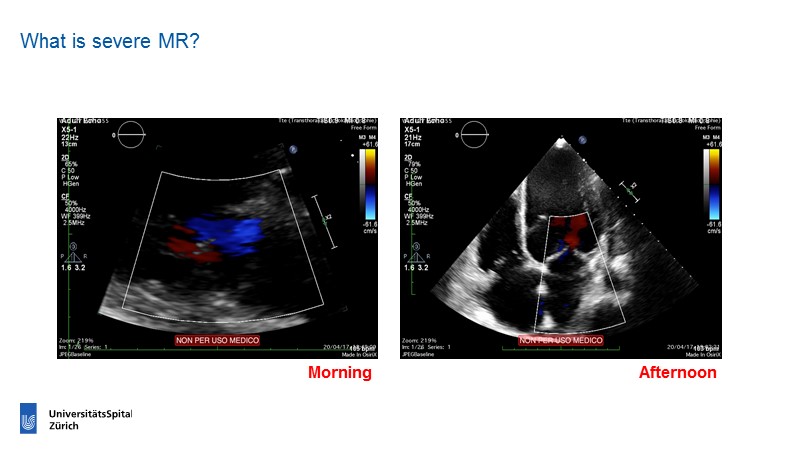

Find out more about how new clinical evidence (MitraFR, COAPT) will shape the future of mitral transcatheter interventions.

- To learn how will new clinical evidence (MitraFR, COAPT) shape the future of mitral transcatheter interventions